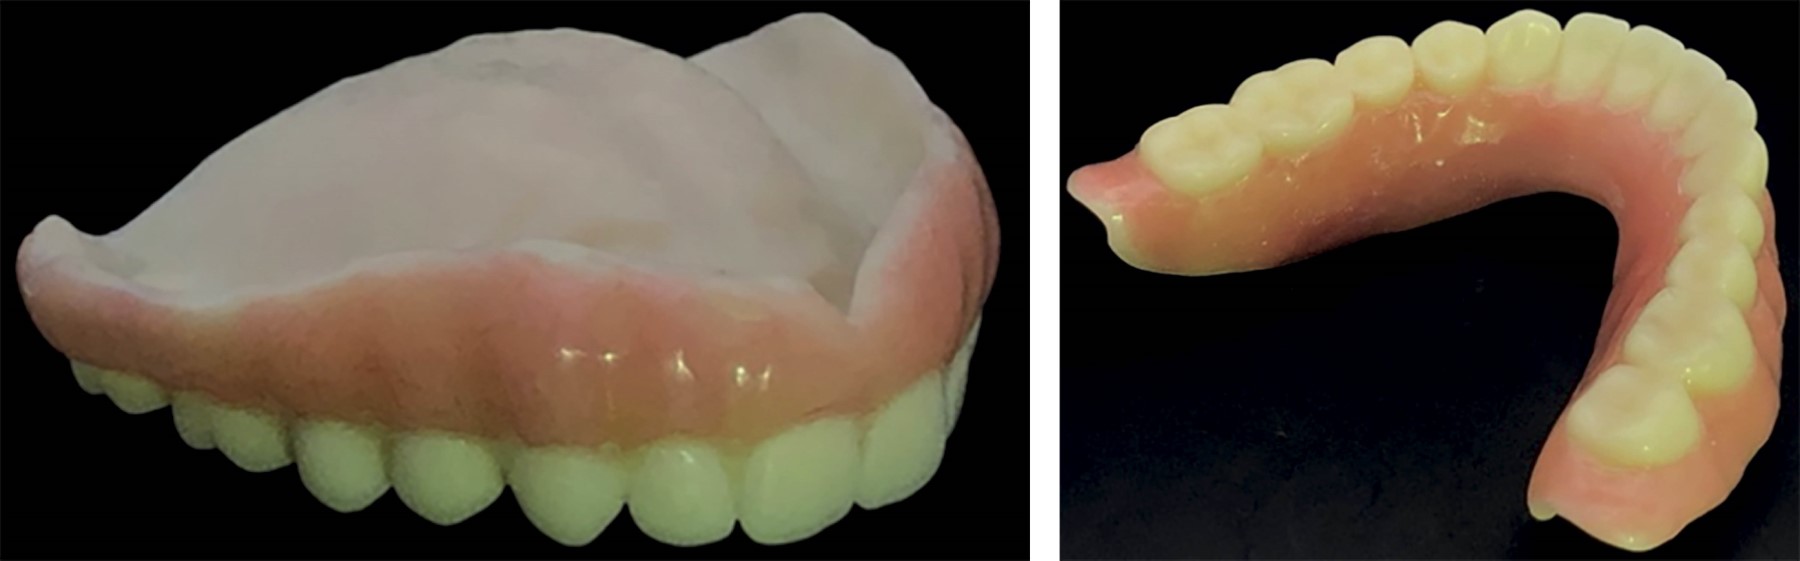

Se imprimieron ambas prótesis inmediatas en resina fotopolimerizada a base de metacrilato color A2 (Temporary CB Resin de la marca Formlabs®) (Figura 3). Se llevó a cabo con la impresora 3D modelo IBEE de la marca UNIZ® utilizando un grosor de capa de 25 micras.

Se caracterizó la prótesis inmediata con acrílico termocurado color R5V. Para evitar superposiciones de acrílico en la dentadura, se colocó vaselina en las piezas dentales y se cubrió con una llave de silicona (se utilizó la marca Speedex®). Al terminar, se recubrió la prótesis en toda su superficie con sellante de composite de alta penetración de la marca PermaSeal® (Figura 3).

Se realizó la entrega de las prótesis inmediatas (Figura 4). Al colocar se utilizó un acondicionador de tejidos para bases y rebases de la marca Softy®. Se colocó el material en la prótesis inmediata superior y posteriormente en la inferior y con ello se le indicó a la paciente que mordiera. Después se realizaron ajustes en la línea de la base de la dentadura y ajustes oclusales (Figura 4).